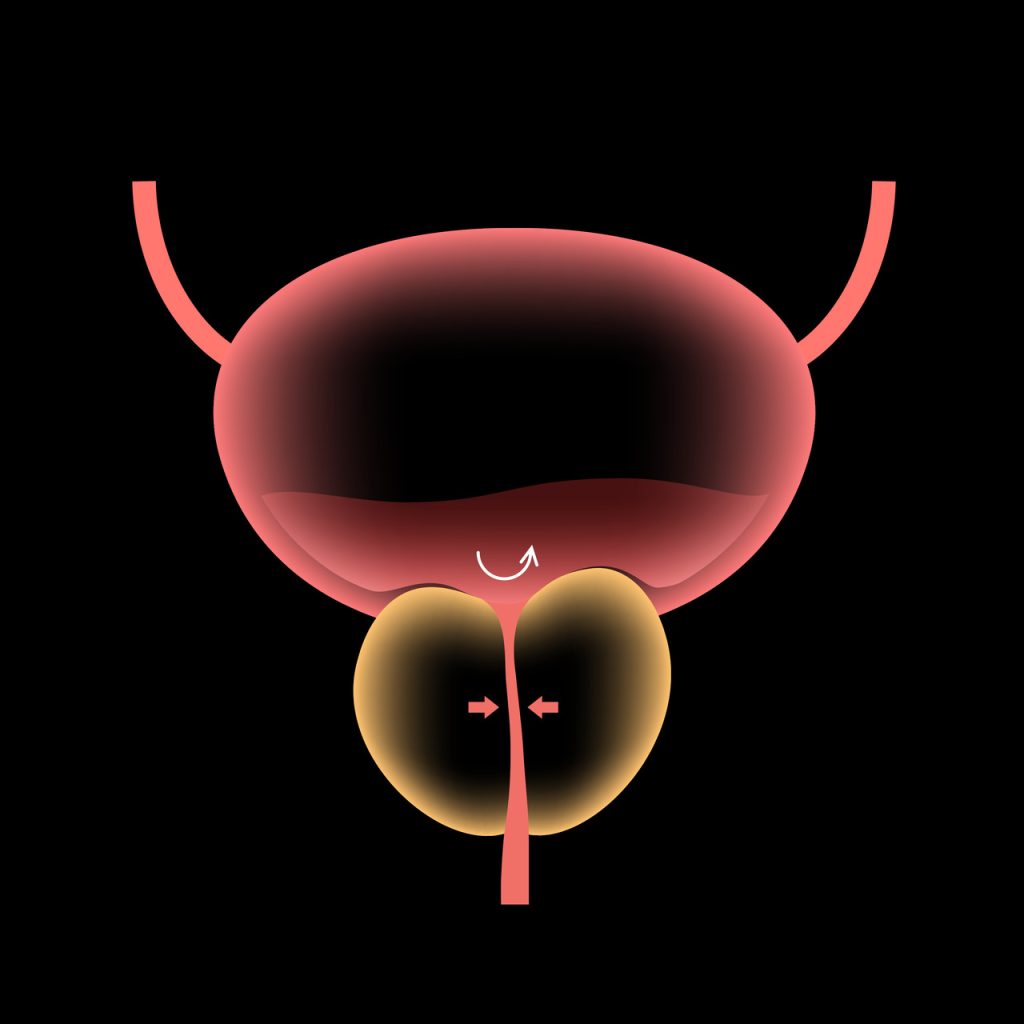

A cirurgia HoLEP é considerada uma das mais eficazes para o tratamento da próstata aumentada, especialmente em casos de hiperplasia prostática benigna.

Com tecnologia a laser, o procedimento remove com precisão o tecido prostático obstrutivo, aliviando sintomas urinários como jato fraco, esforço para urinar e micção frequente.

Por ser feita pela uretra, sem cortes, a recuperação é mais confortável e o tempo de internação menor.

Além disso, o HoLEP apresenta menos sangramento e menor taxa de reintervenção a longo prazo em comparação com técnicas tradicionais como a RTU.